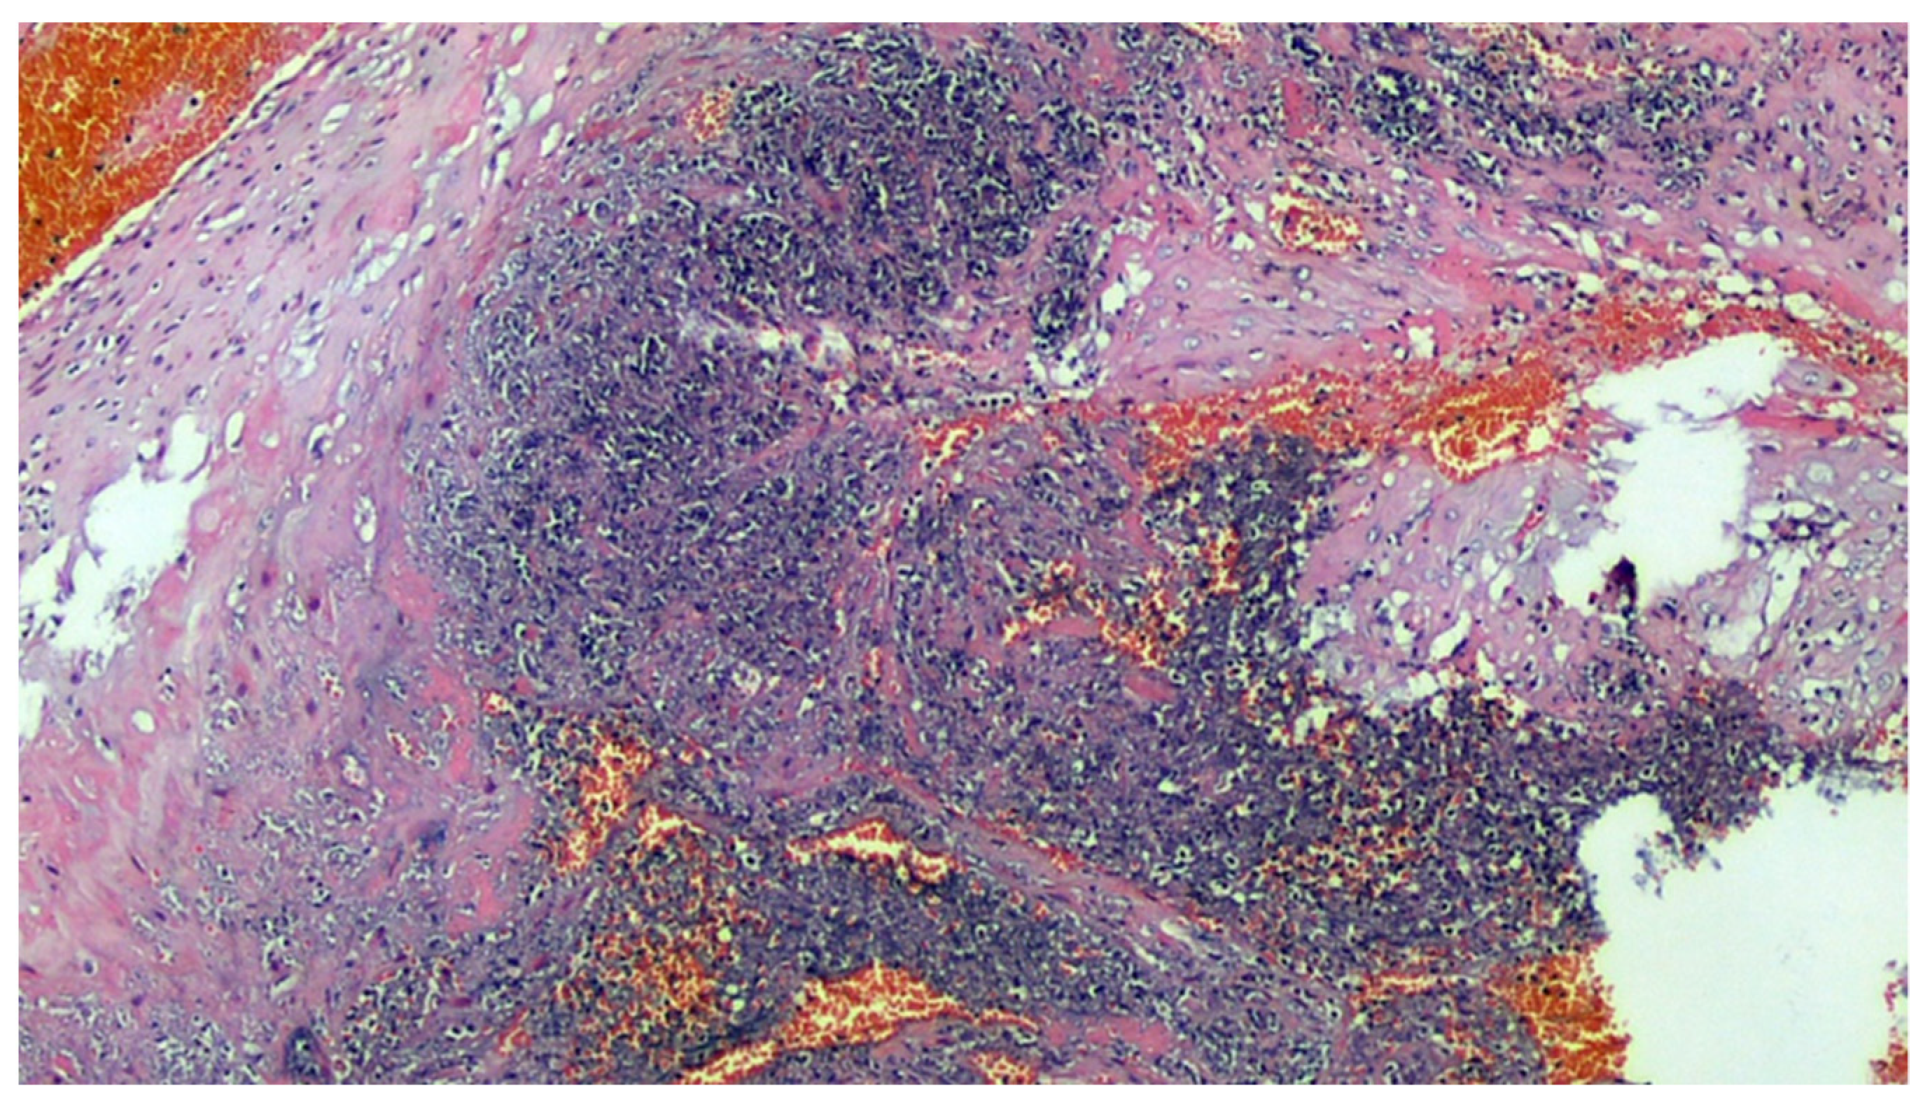

Figure 5.

Histological section of the main villus: the artery has a thickened muscular wall, marked intimal fibrous thickening (probable organization of arterial thrombus), clear reduction of the lumen, and recent thrombosis of the residual lumen. H&E, 200×.